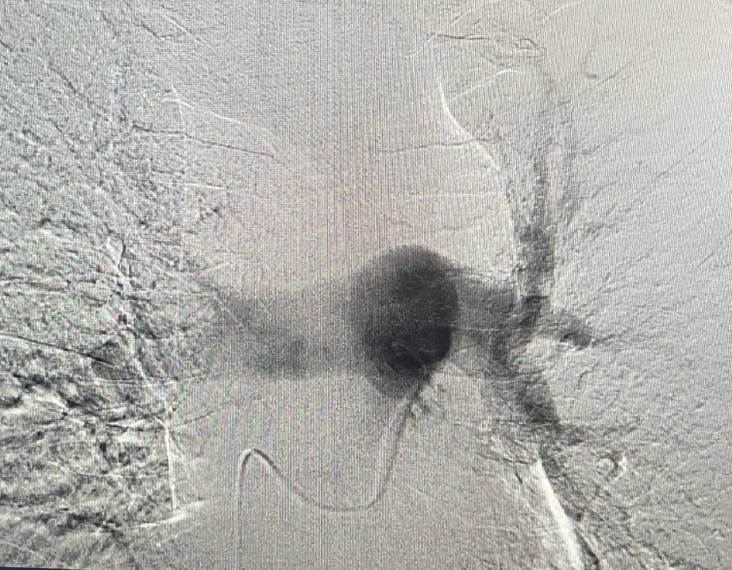

Figure 1. Right initial angiogram.

Figure 2. Left initial angiogram.

A man in his mid-40s with bilateral PE was transferred to our facility. A CTA was performed to confirm the PE, along with pre- and postechocardiograms (Figure 1 and Figure 2). The patient had no known history of previous DVT or PE. Heparin was stopped 8 hours prior to treatment, and 3,000 units were administered intraprocedurally. Diagnostic testing revealed a troponin of 869 mg/mL and hemoglobin of 12.7 g/dL. The patient presented with a BP of 137/97 mm Hg and was tachycardic with a HR of 120 bpm.